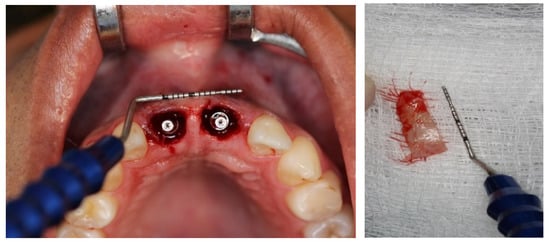

2.5. Surgical Procedures

3. Results

Result and Follow-Up